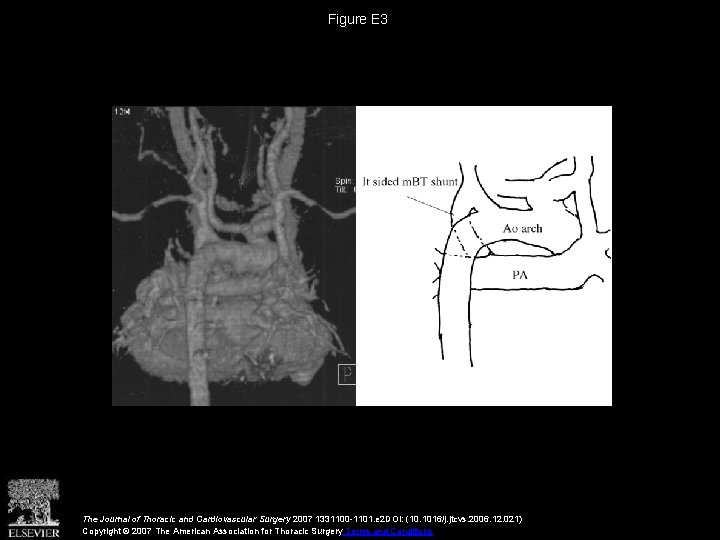

Figure E 3 The Journal of Thoracic and Cardiovascular Surgery 2007 1331100 -1101. e

Figure E 3 The Journal of Thoracic and Cardiovascular Surgery 2007 1331100 -1101. e 2 DOI: (10. 1016/j. jtcvs. 2006. 12. 021) Copyright © 2007 The American Association for Thoracic Surgery Terms and Conditions